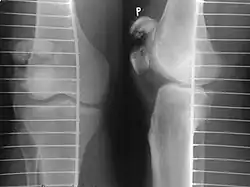

The patella can break in various ways depending on the way it is injured, and into two or more pieces.[1] Types include transverse, the most common, with one fracture line;[5] marginal; osteochondral; and the rare vertical type, or stellate, where a direct compression force gives rise to a comminuted pattern.[5][7] Patella fractures can be further classified as displaced, where the broken ends of bone do not line up correctly and separate by more than 2mm, or undisplaced and stable where pieces of bone remain in contact with each other.[1][7] If fragments of patella bone stick out from the skin it is known as an open patella fracture, and closed if the overlying skin is intact.[1]

-

Transverse fracture of patella -

Comminuted fracture of patella -

Osteochondral fracture of patella -

Vertical patella fracture